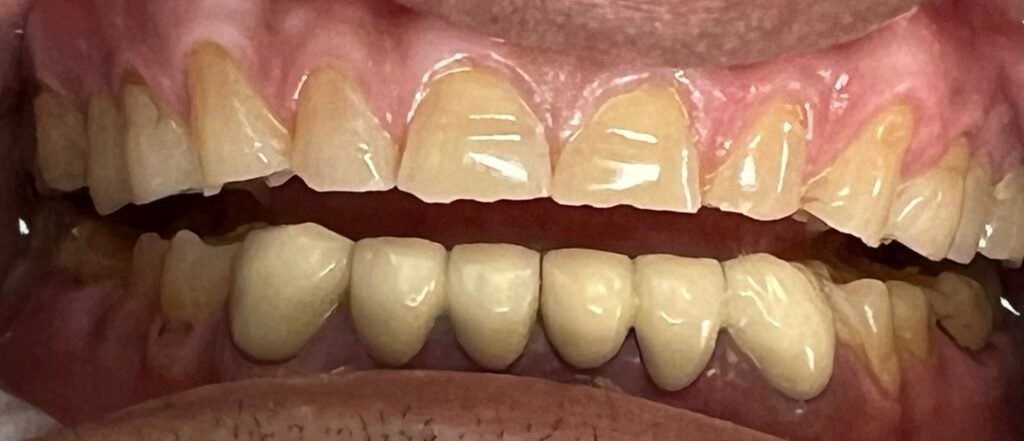

Stop the progression of gum disease and preserve your natural teeth with Gum treatment in Sunnyvale at Huh Dental Wellness

Periodontal diseases are infections of the gums that gradually destroy the support system of your natural teeth. It is a startling fact that adults over 35 lose more teeth to gum disease than to cavities, with three out of four adults affected at some point in their lives. At Huh Dental Wellness in Sunnyvale, we focus on early diagnosis and proactive gum treatment to preserve your smile for a lifetime.

Understanding the Plaque Factor